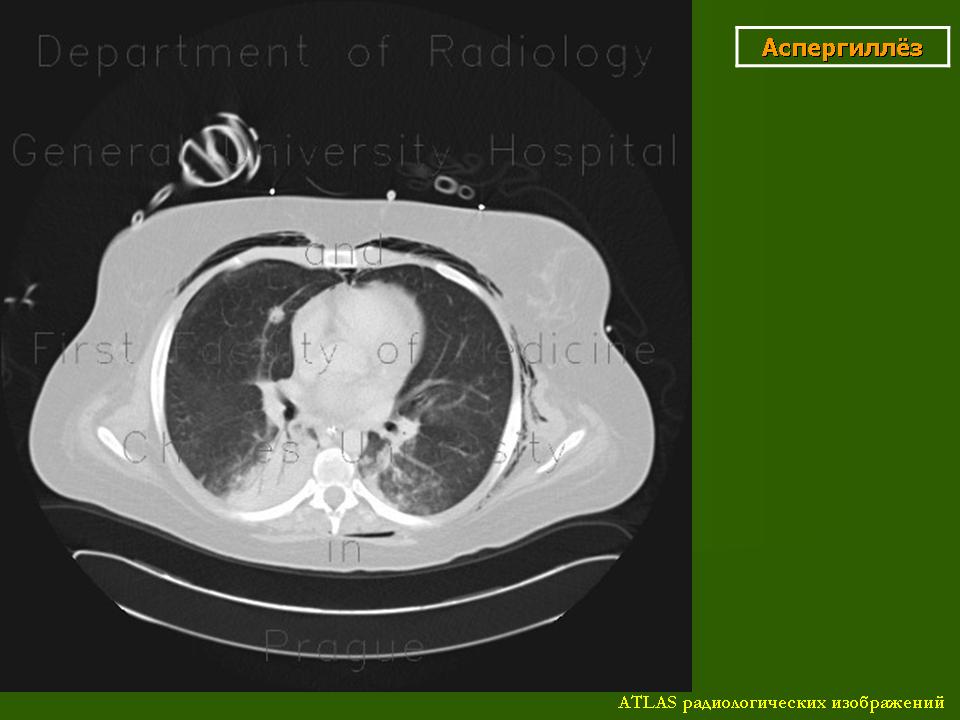

При вдыхании спор возникает первичная инфекция, при которой наблюдаются изменения в легких. Иногда микробы могут проникнуть через кожу. Первичная инфекция легких обычно протекает бессимптомно. Клинические симптомы развиваются только в 30% случаев и инфекция диагносцируется на основании положительной кожной реакции с кокцидиоидином. При рентгенологическом исследовании можно обнаружить только нежные затемнения в области гилюсов. Изменения эти исчезают в течение 1-2 недель. Чаще всего наблюдаются воспалительные инфильтраты, которые при рентгенологическом исследовании представляются в виде мягких однородных затемнений, распространяющиеся от гилюса в нижние и средние легочные поля. Чаще всего такие затемнения исчезают в течение 1-2 недель.

Для легких характерны инфильтраты, имеющие диаметр 2-3 см и нередко располагающиеся в средних и нижних легочных полях. Чаще всего инфильтраты в легких бывают единичные, но бывают и множественные, напоминающие метастазы или первичный туберкулез. Очаги имеют спокойный характер, через несколько месяцев рассасываются или распадаются, образуя тонкостенные полости.

При кокцидиоидомикозе увеличение медиастинальных и гилюсных лимфатических узлов бывает не часто и, обычно связано с инфильтрацией легочной ткани при остром течении болезни. Иногда наблюдается небольшой экссудат, располагающийся в ребернодиафрагмальном синусе, который быстро всасывается. Большие экссудаты бывают редко.